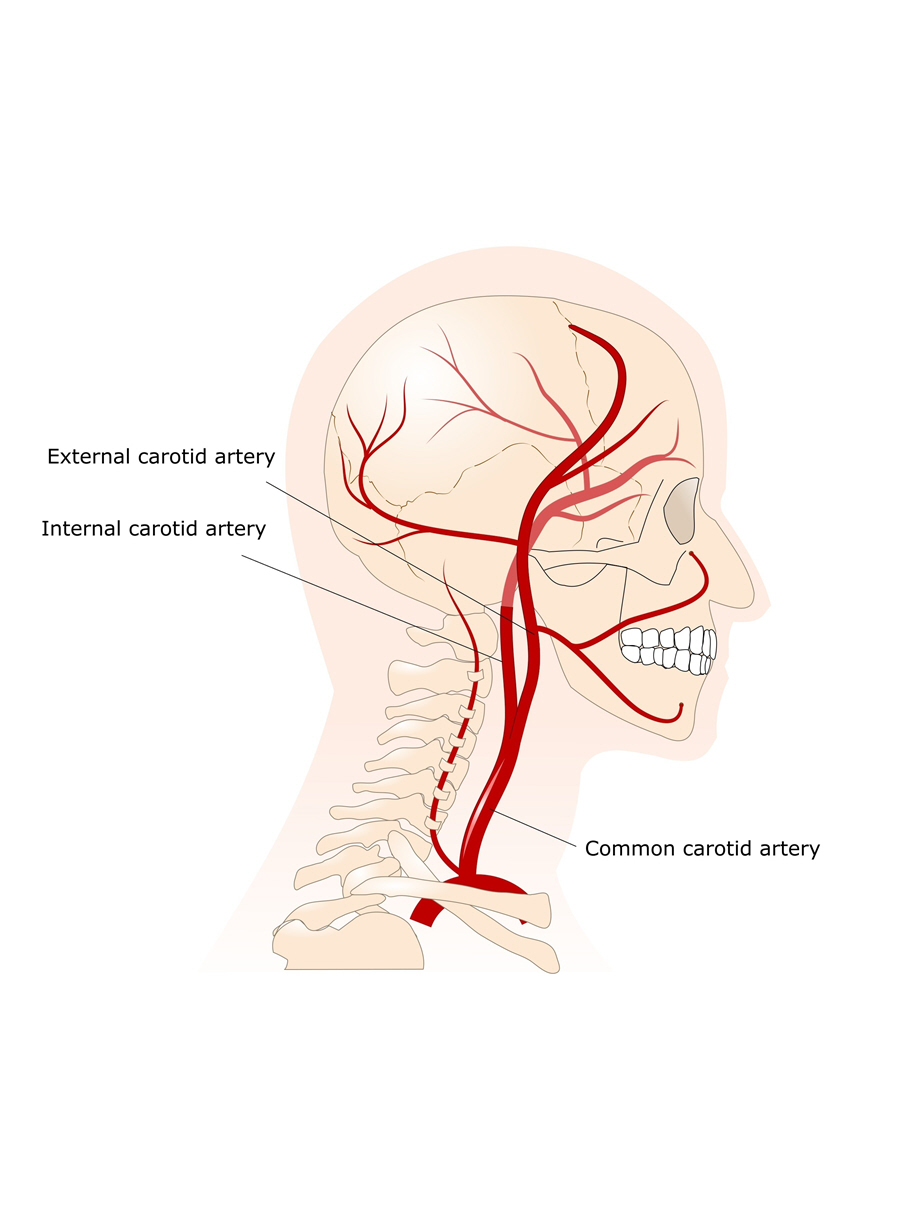

Carotid Arteries Eye Patient

https://eyepatient.net/Docs/article/Carotid_Arteries_01.jpg

Carotid Artery Pain Symptoms

Carotid Artery Pain Symptoms

Carotid Artery Pain Symptoms

Carotid Artery Pain Symptoms